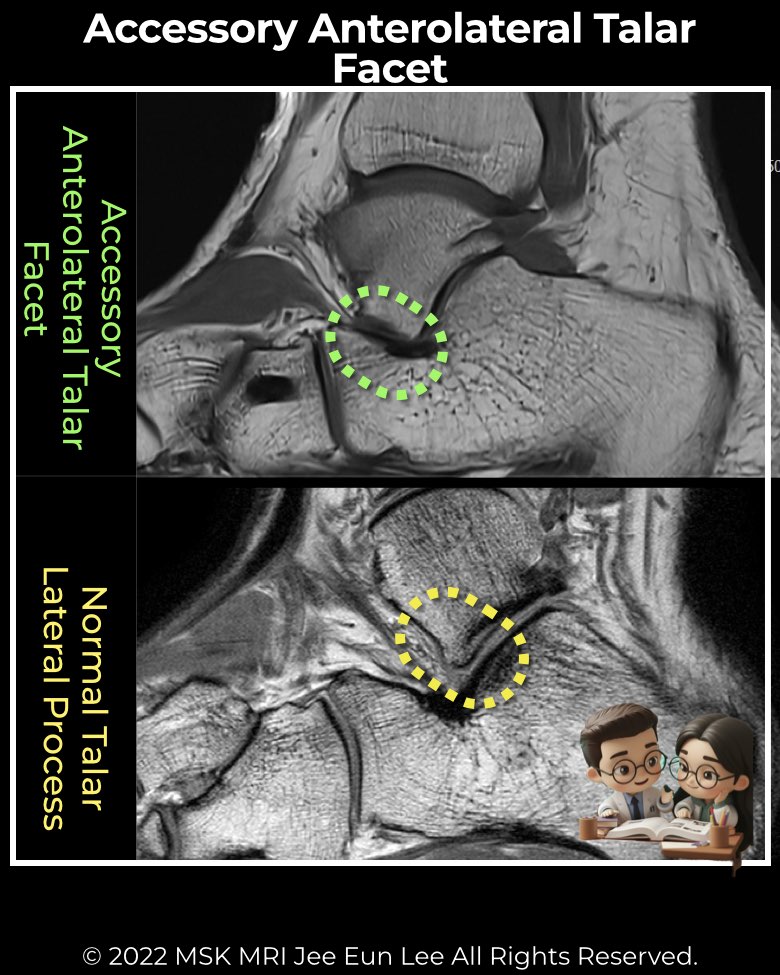

The AALTF is an anatomic variant where the posterior talar facet extends anteriorly, wrapping around the lateral talar process into the sinus tarsi. It represents an accessory talocalcaneal articulation, not a true separate ossicle.

- MRI findings: Best modality for detection. Look for:

• Accessory facet cartilage extending anterior to lateral talar process.

• Associated FABME (focal abutting bone marrow edema).

• Sinus tarsi edema. - Pitfall in management: Persistent lateral hindfoot pain may remain after coalition resection if an unrecognized AALTF is present.